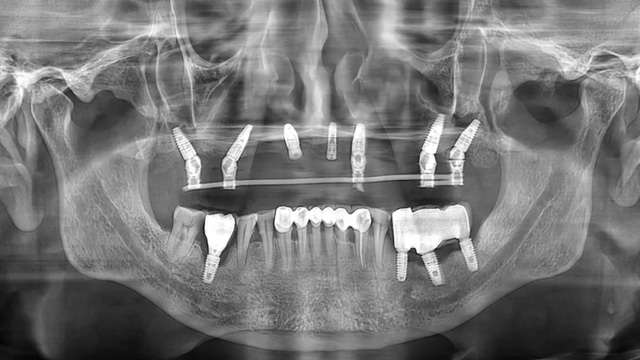

“我们通过ALL-ON-6即刻种植即刻修复,来恢复他上半口的咀嚼功能。因为他骨质骨量都比较差,在手术同期植入了大量骨粉,部分位置采用了倾斜种植。”

由于骨质条件无法承受常规种植体的长度和直径,易华波医生为沈老师选择了ITI瑞锆种植体,“他牙槽骨的垂直高度和水平宽度都不足,只能选择这种比常规种植体更细、更短的型号,种植后才能实现良好的骨结合,达到和常规种植体一样的远期效果。”

治疗后口腔全景片